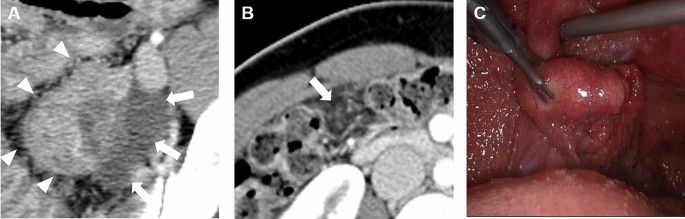

Table 2 shows the characteristics of CT imaging features of TB peritonitis and peritoneal carcinomatosis. Women with TB peritonitis had more changes in their fallopian tube, more peritoneal micronodules, and fewer macronodules than women with peritoneal carcinomatosis (64.0% vs. 8.8%, pā<ā0.001; 52.0% vs. 23.5% and 48.0% vs. 76.5%, pā=ā0.024). In the univariate logistic regression analysis using significantly different imaging features between the two diseases, changes in fallopian tubes, no adnexal mass, and peritoneal micronodules were significantly associated with TB peritonitis (pāā¤ā0.027). In the subsequent multivariate analysis, changes in fallopian tube and peritoneal micronodules were independent parameters associated with TB peritonitis (pāā¤ā0.012) (Table 3). When we combined the two independent imaging parameters, the AUC for differentiating TB peritonitis from peritoneal carcinomatosis was 0.855, with a sensitivity of 88.0% (95% confidence interval [CI], 68.8ā97.5]. The specificity was 67.7% (95% CI 49.5ā82.6), the positive predictive value was 66.7% (95% CI 54.6ā76.9), the negative predictive value was 88.5% (95% CI 72.1ā95.8), and diagnostic accuracy was 77.8% (95% CI 65.1ā87.6). The kappa values for changes in fallopian tube and peritoneal micronodules were 0.708 and 0.778, respectively, which indicated a good agreement for the imaging features. A representative case of TB peritonitis in a CT scan and diagnostic laparoscopy is shown in Fig.Ā 3.

A case of TB peritonitis in a 28-year-old Korean woman. (A) In CT, there were bilateral ovarian masses [Rt. 4.9Ā cm (not shown), Lt. 4.5Ā cm (arrowheads)] in the pelvic cavity with hydrosalpinx (arrows). (B) There were diffuse peritoneal infiltration and nodularity without discrete peritoneal nodules or massesā>ā5Ā mm, considered peritoneal micronodules (arrow). The levels of CA125 and CA19-9 were 104.4Ā IU/mL and 1.3Ā IU/mL, respectively. Laparoscopic bilateral salpingectomy and left ovarian cystectomy were performed. (C) Diagnostic laparoscopy showed multiple miliary nodules on the uterine and peritoneal surfaces.